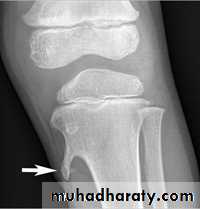

Osteochondroma (cartilage capped exostosis):

Commonest benign tumor of bone.

Occurs during bone growth in adolescence.

Starts as cartilaginous overgrowth at the edge of the epiphysis and grow outside the bone on the same direction (towards diaphysis), its base later on ossify and show on x-ray as an exostosis (either narrow base-pedanculated or wide base-sessile). Its growth continues with the bone and stops as the bone stops growing, any enlargement after that (especially if associated with pain) considered serious and regarded as malignant transformation until proved otherwise.

It can be single or multiple (multiple familial osteochondrom, congenital achlasis).

Pain or lump is the usual presentation, there is pain due to an overlying bursa or impingement on soft tissues, or it may affect nearby joint or tendon function, sometimes it press on nearby important structures as vessel or nerve. Paraesthesia may due to stretching of an adjacent nerve.

Sometimes accidentally discovered by x-ray

Incidence of malignant transformation is about 1% in single and 6% in multiple osteeochondroma.

X-ray shows well-defined exostosis at the bone ends mainly around the knee.

Any increase in size or pain after puberty must be concederd malignant transformation until proved otherwise. It can change to chodrosarcoma or osteosarcoma.

Treatment is by local excision of the exostosis.